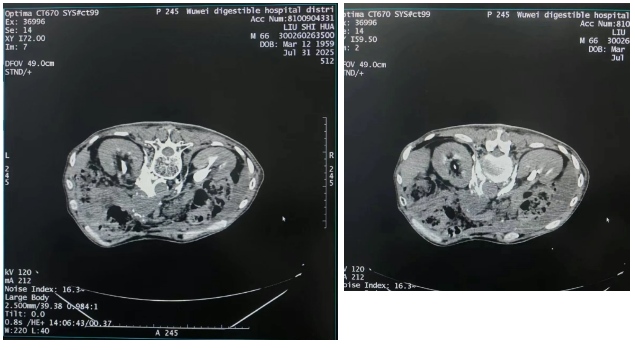

接受CT引导下腹腔神经丛毁损治疗后,刘先生口服盐酸羟考酮缓释片10mg Q12h,疼痛评分从8分(重度)降至1分(轻度),呕吐、便秘基本缓解,生活质量明显改善。